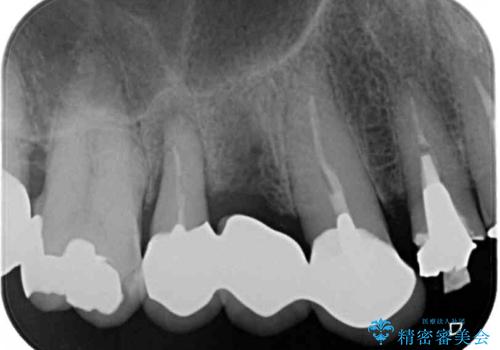

- 歯が割れてしまったとのことで来院された患者様です。

痛みは特にありませんでしたが、以前から歯が割れていることを指摘されており、徐々に不快感が増してきたとのことでした。

咬合力が強く、抜歯となる破折歯の前後の歯はいずれも神経が除去された歯であることから、ブリッジでは長期的な予後に不安があると判断されましたが、前後の銀歯も一気にきれいにしたいとのことで、オールセラミックブリッジによる補綴治療を行うこととしました。

ブリッジの支台が破折した場合にはインプラント治療が必須となるため、咬合力による破折を避ける目的で、就寝時のマウスピース装着が非常に重要となります。